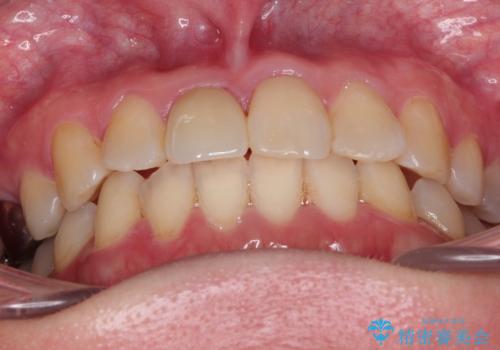

インビザラインにて矯正治療後の前歯のセラミッククラウン治療

- 前歯の歯並びが気になるとのことで来院されました。

右上の1番目の歯が内側に入り込んでしまっており、その歯がの先端がすり減ってしまっていました。

インビザラインによる矯正治療で前歯の歯並びを改善し、セラミッククラウン装着により歯の形態の回復をする計画としました。

矯正とセラミックを併用することで、より完成度の高い状態に仕上げることができました。